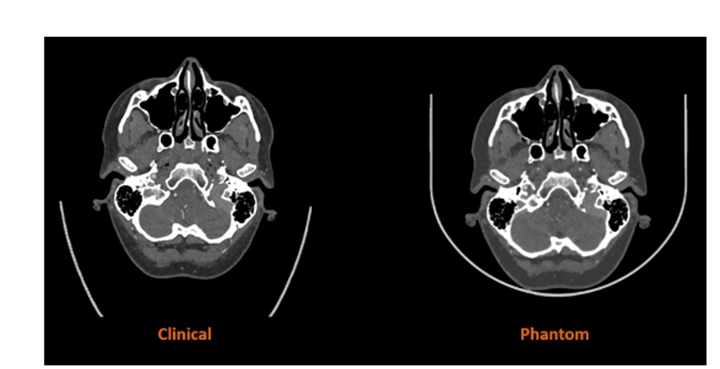

Stratasys擴(kuò)大醫(yī)學(xué)影像用防射線3D打印材料的應(yīng)用范圍 1天前

2025年12月8日,3D打印機(jī)OEM廠商Stratasys宣布可阻礙射線穿透的RadioMatrix 3D打印材料現(xiàn)已在美國全面上市。這種材料此前僅在有限范圍內(nèi)使用,如今可供醫(yī)療機(jī)構(gòu)、醫(yī)療器械制造商和研究機(jī)構(gòu)廣泛用于先進(jìn)的醫(yī)學(xué)成像、教育和培訓(xùn)等領(lǐng)域。據(jù)Stratasys公司聲稱稱,RadioMatrix是第一種也是唯一一種能夠精確控制放射阻射性的3D打印材料,可以創(chuàng)建在X射線成像下具有一致且可調(diào)可見性的患者特定模型。